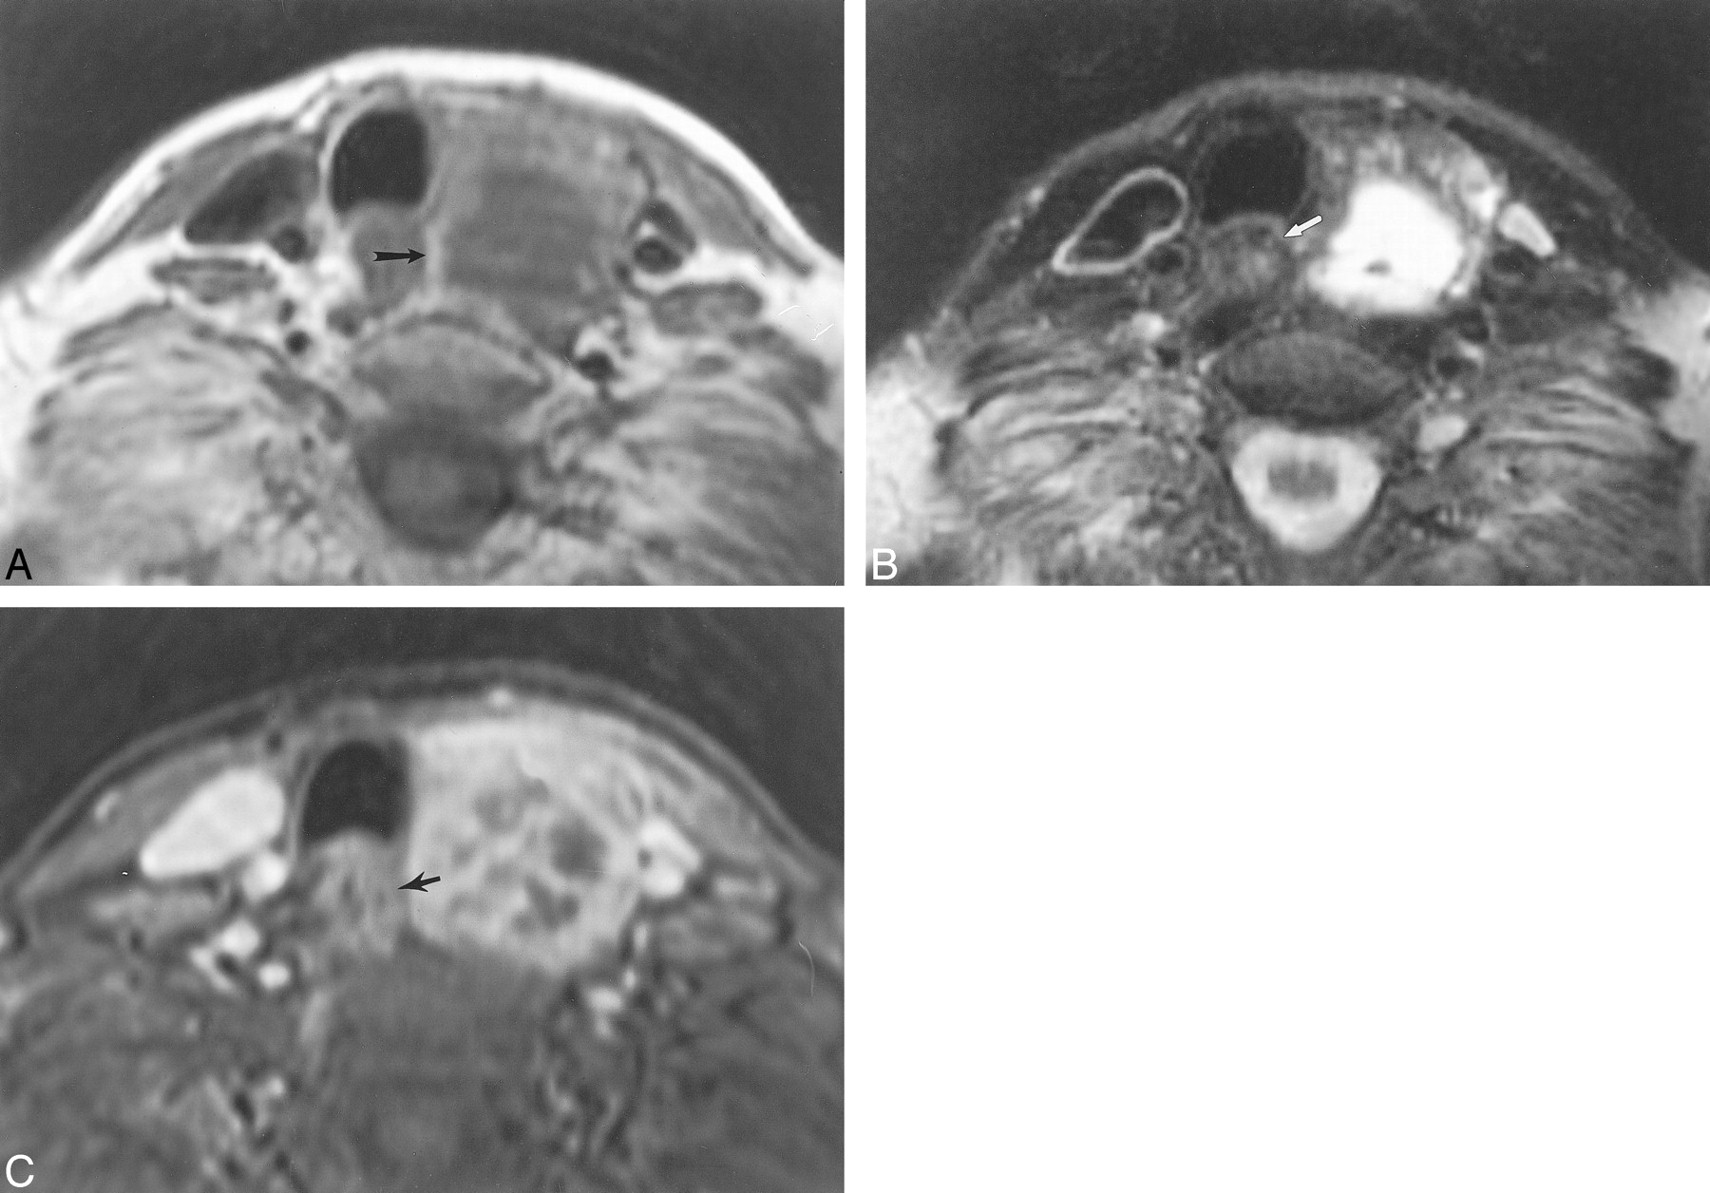

This 68-year-old woman with a benign, left, thyroidal multinodular goiter demonstrates the normal MR imaging appearance of the adjacent esophagus.

A, Axial T1-weighted image (500/16 [TR/TE]) shows an intact fat plane (arrow) between the esophagus and the mass. The thyroid mass is adjacent to the esophagus, and the esophageal lumen is collapsed.

B, Axial T2-weighted image (3500/84) shows normal hypointense signal of the wall musculature of the esophagus (arrow).

C, Axial enhanced 3D FMPSPGR image (220/27; flip angle, 90o) shows mild enhancement of the mucosal lining of the esophageal wall (arrow).